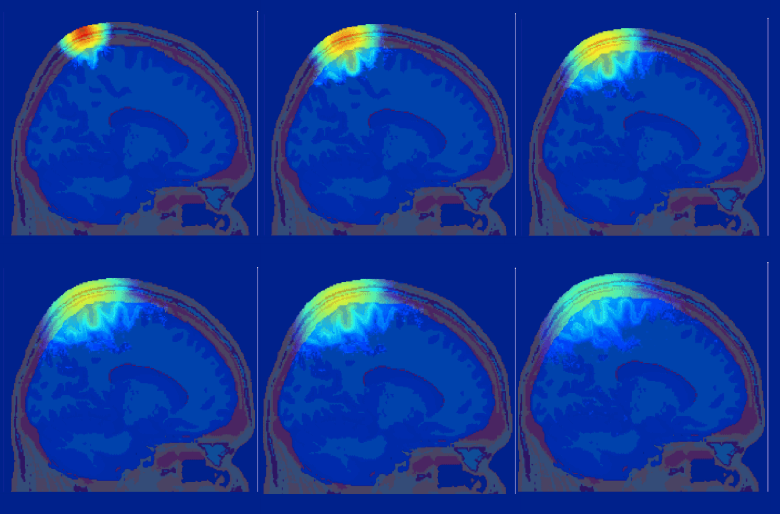

Researchers at Northeastern University are using computers at the MGHPCC to improve the performance of a popular medical imaging tool which estimates 3D light distribution in biological tissue using GPU technology to simultaneously simulate the paths of large numbers of independent photons. MORE